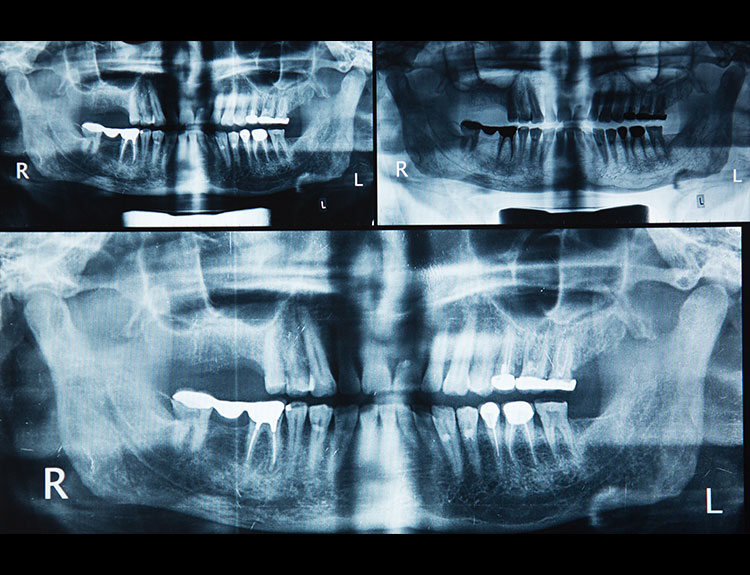

Dental implants are artificial tooth roots made of medical-grade titanium that are surgically placed into the jawbone. Once the implant integrates with the bone, a crown is fixed on top, giving you a strong, natural-looking replacement tooth.

When compared to bridges or dentures, dental implants offer unmatched comfort and longevity.